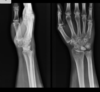

Fratura de Chaffeur

Fratura do processo estilóide do rádio.

Quais fraturas tem relação com a queda com a mão estendida (FOOSH)?

Fratura do escafóide

Fratura de Colles

Fratura de Monteggia

Fratura de Galeazzi.